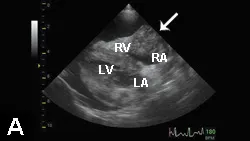

P**hysical ExaminationExamination findings included muffled heart sounds, poor peripheral pulses, pale mucous membranes with a CRT of 2 seconds, rectal temperature of 98.7°F, and distal extremities cool to the touch. ECG suggested ventricular premature contractions. Echocardiography revealed pericardial effusion and a right atrial mass (Figure 1**).

Figure 1. Echocardiography revealed pericardial effusion (asterisk) and a right atrial (RA) mass (arrow). (LA = left atrium, LV = left ventricle, RV = right ventricle)